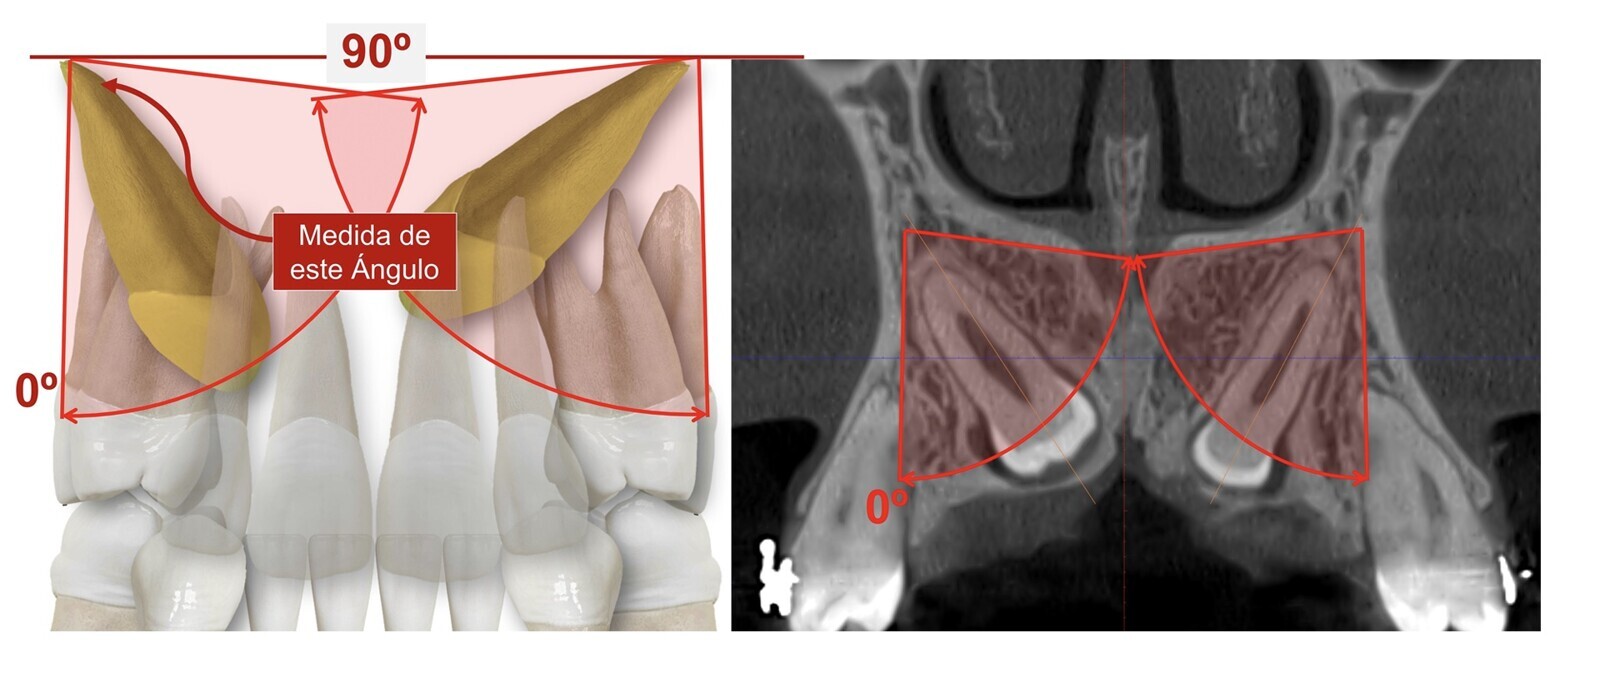

Diagrama que muestra que los cortes oclusales pueden tener una relación armoniosa de vecindad entre el canino con los incisivos y premolares o presentar signos de reabsorción externa de las raíces vecinas.

En el plano frontal (figura 4) hay que valorar la angulación del canino y la altura de su corona. Medir la angulación se puede realizar a partir de una perpendicular al plano transversal maxilar, siendo el ángulo de 0º cuando el canino en cuestión está vertical y de 90º cuando el canino está completamente horizontal y está paralelo al plano transversal maxilar referido. A mayor ángulo, mayor puntaje negativo a la hora de valorar la dificultad del caso. Para valorar la altura de la corona (figuras 5 y 6), hemos establecido aleatoriamente tres áreas rectangulares:

Los cortes transversales de los caninos nos orientan sobre su verdadera inclinación. Los cortes oclusales (figura 9) muestran la relación de vecindad del canino con los incisivos y premolares y si ésta es armoniosa (espacio de seguridad suficiente alrededor de la corona del canino) o presenta signos preocupantes de reabsorción externa de las raíces vecinas.

Figura 9. Los cortes oclusales muestran la relación de vecindad del canino con los incisivos y premolares y si ésta es armoniosa o presenta signos preocupantes de reabsorción externa de las raíces vecinas.

Sobre estos cortes oclusales también establecemos áreas poligonales de mejor (área I) a peor pronóstico (área III), según delimiten las zonas normales de emergencia canina o zonas muy alejadas. La suma de la angulación y la valoración objetiva de cada área ya nos va orientando sobre la mayor o menos dificultad del caso.